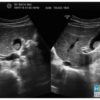

* Sỏi mật

– Là cấu trúc tăng âm kèm bóng cản, hình tròn hoặc bầu dục nằm trong túi mật, có thể thay đổi vị trí theo tư thế bệnh nhân.

– Các viên sỏi nhỏ có thể không tạo bóng cản.

– Nếu sỏi kẹt cổ túi mật hoặc túi mật viêm teo, túi mật xẹp, viêm teo thành túi mật ôm sát viên sỏi, sỏi quá lớn chiếm toàn bộ túi mật thì không thay đổi vị trí khi thay đổi tư thế.

+ Một số viên sỏi bám chặt vào thành túi mật hoặc sỏi kẹt cổ tủi mật hoặc túi mật teo nhỏ thì không di động khi thay đổi tư thế. Khi sỏi nhỏ bóng lưng không rõ cần phân biệt với Polyp.* Sỏi bùn